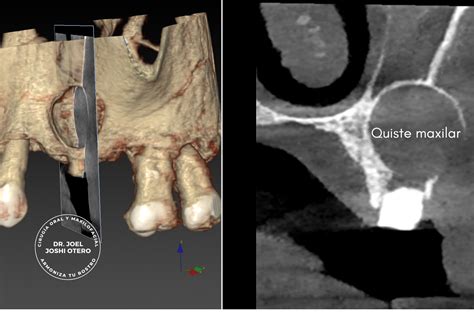

En la ortopantomografía (radiografía en 2D de toda la boca) el quiste maxilar se observa como una zona oscura y redondeada en forma de bolsa. Generalmente es necesario realizar una radiografía para diagnosticar esta patología que se manifiesta a través de una zona oscura en el hueso.